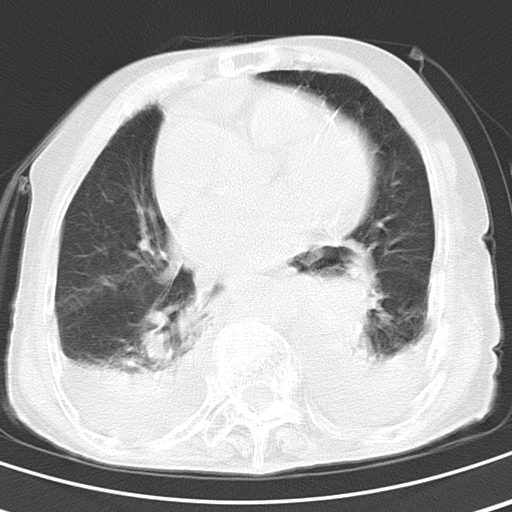

标题: CT21467:女,93岁,摔伤后检查。

女,93岁,摔伤后检查。

右肺炎症,心功能不全伴双侧胸腔积液,右下肺膨胀不全,食管裂孔疝,冠脉钙化,心包少量积液,左侧肋骨骨折,请上传骨窗.

右侧锁骨\\肩胛骨骨折、右侧湿肺,心功能不全伴双侧胸腔积液,右下肺膨胀不全,左膈破裂或食管裂孔疝,冠脉钙化,心包少量积液,请上传骨窗.

右肺炎症,心功能不全伴双侧胸腔积液,右下肺膨胀不全,食管裂孔疝,冠脉钙化,心包少量积液,左侧肋骨骨折,右肩甲骨粉碎性骨折。93岁,高寿哇!

右肺炎症,心功能不全伴双侧胸腔积液,右下肺膨胀不全,食管裂孔疝,冠脉钙化,心包少量积液,左侧肋骨骨折,右肩甲骨粉碎性骨折。